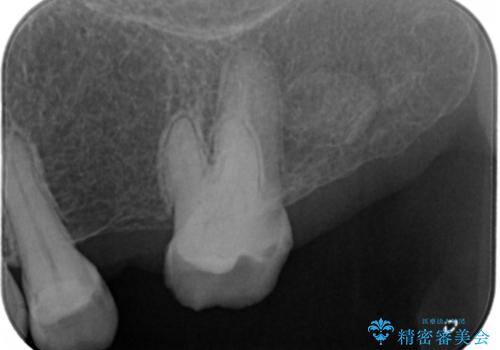

- 左上臼歯部に保険のブリッジを入れていたがすぐに取れてしまったので自費治療でのやり変えを希望された患者様です。

インプラントとブリッジを提案しましたが時間をかけたくないとのことだったので、ブリッジでの治療を選択しました。

左上6番が大きく傾いているため、露髄や痛みが出る可能性を事前にお伝えしています。